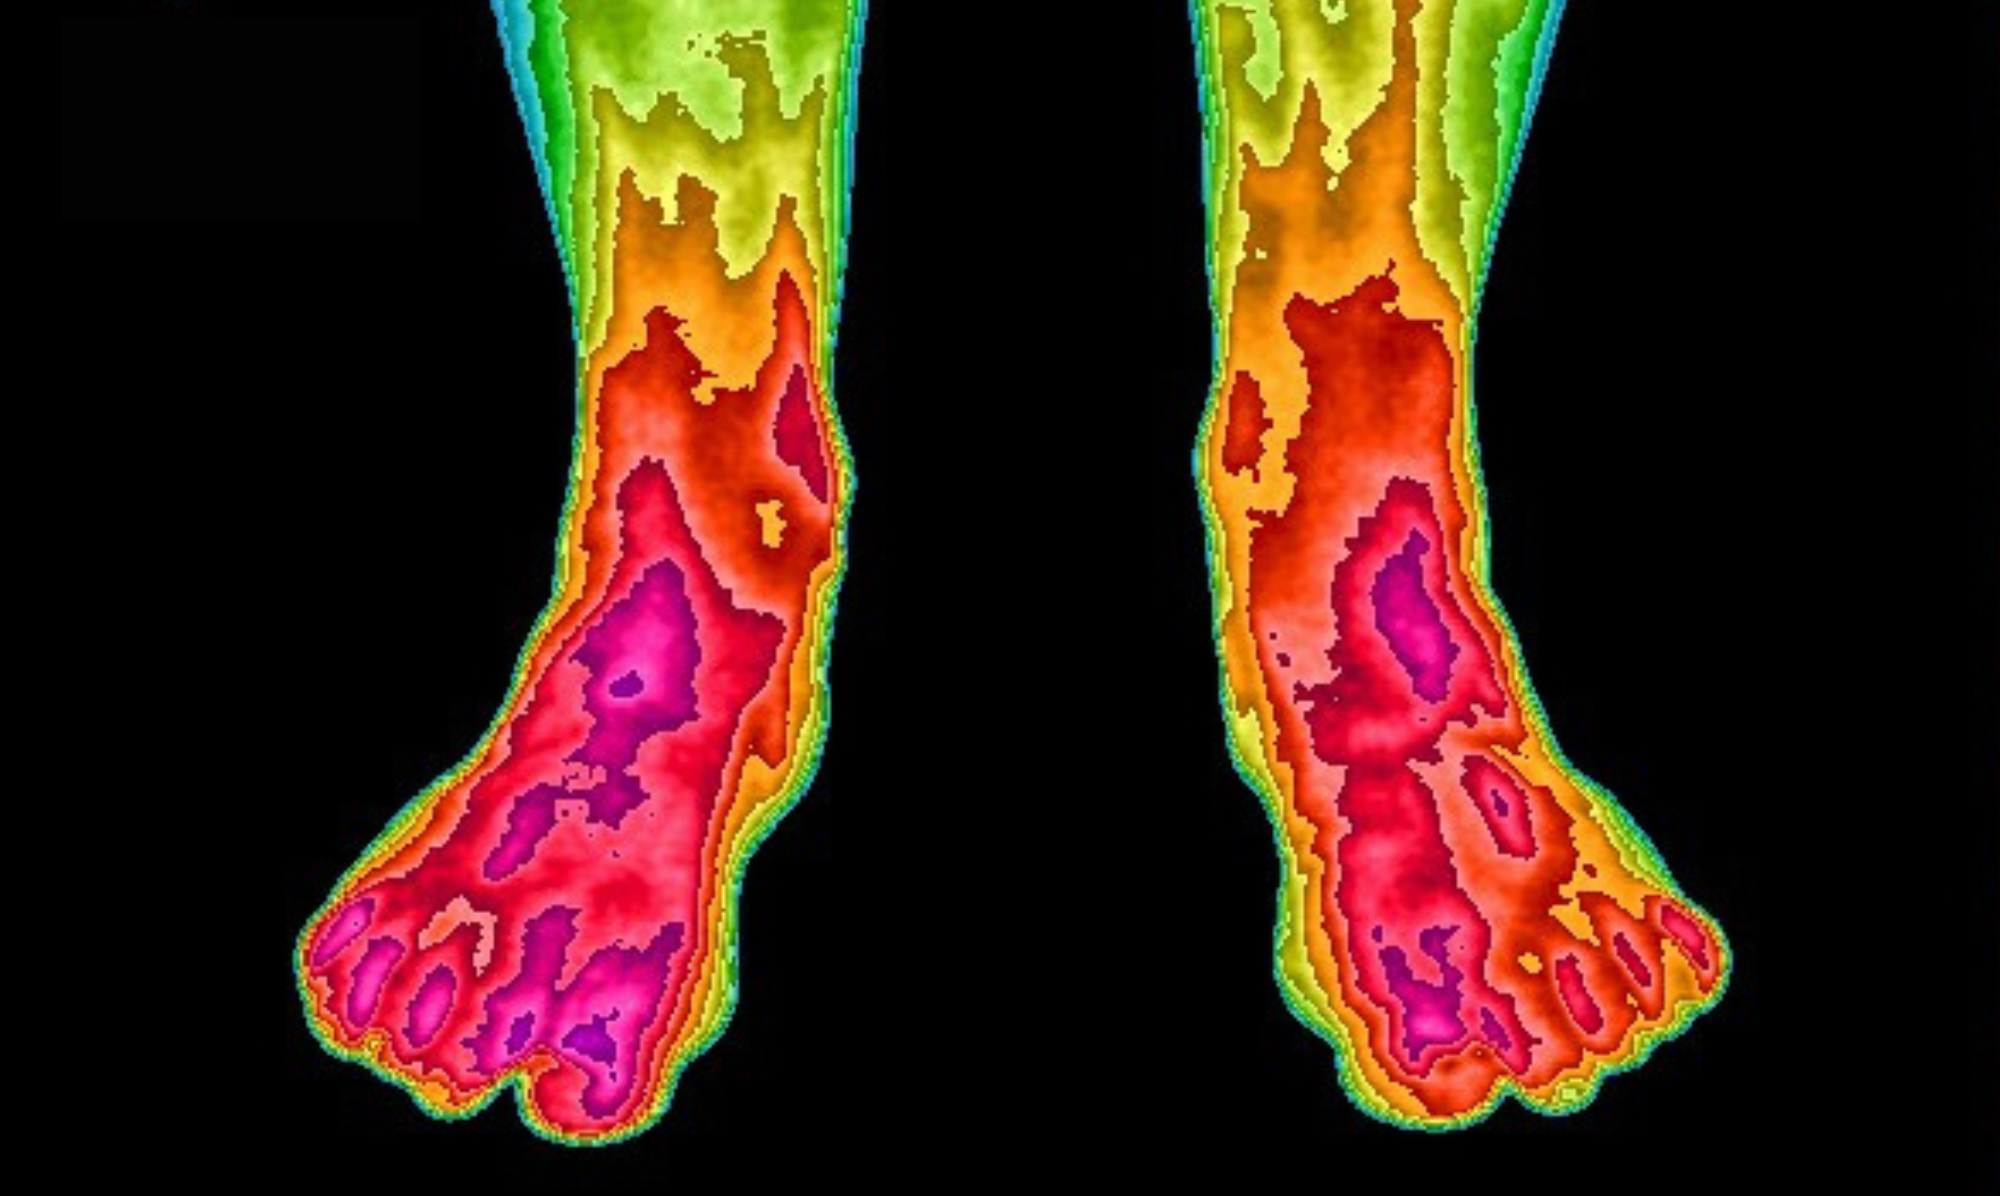

More than 26 scientific studies have examined grounding's positive effects on the human body. The infrared images shown here demonstrate blood flow changes after using our Earthing Mattress Cover for two weeks. Initially, toe circulation was nearly non-existent. Following the grounding period, healthy circulation returned to normal levels. This represents just one example from the extensive research conducted.